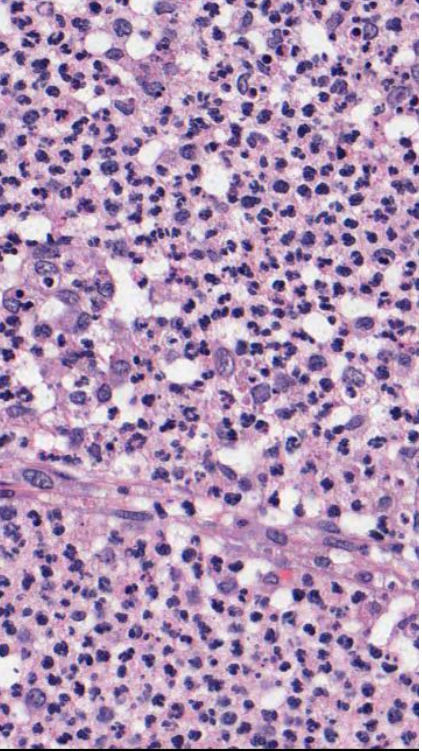

name the biological process shown in this image

acute inflammation

neutrophils !!